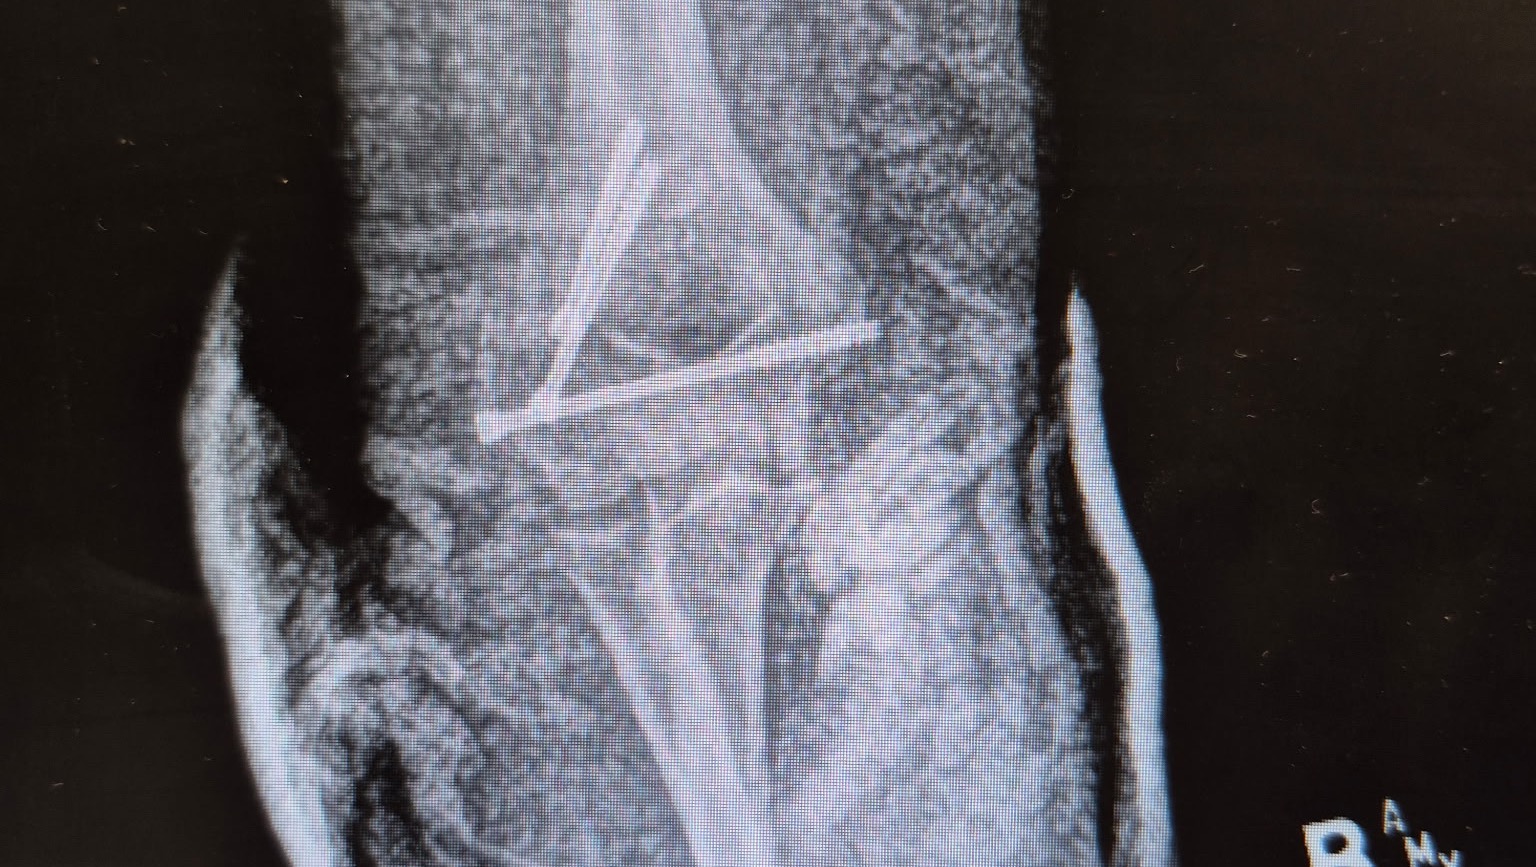

My name is Allie Koon, and in mid-January, I managed to fall on some black ice and both dislocate and fracture my right elbow. The injury required surgery to place three screws into my arm.